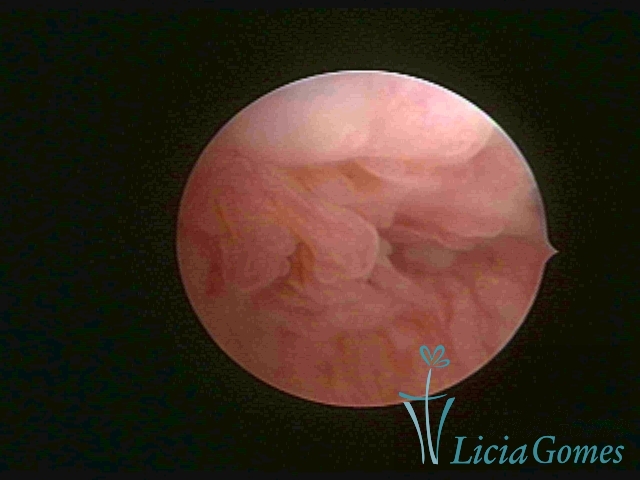

First part or proximal section or lower section:

During the proliferative phase, a light, crystalline mucus with a low adherence to the scope is found. The crypts and buds are a little swelled and vascularized, microvesicular, resembling grape clusters.